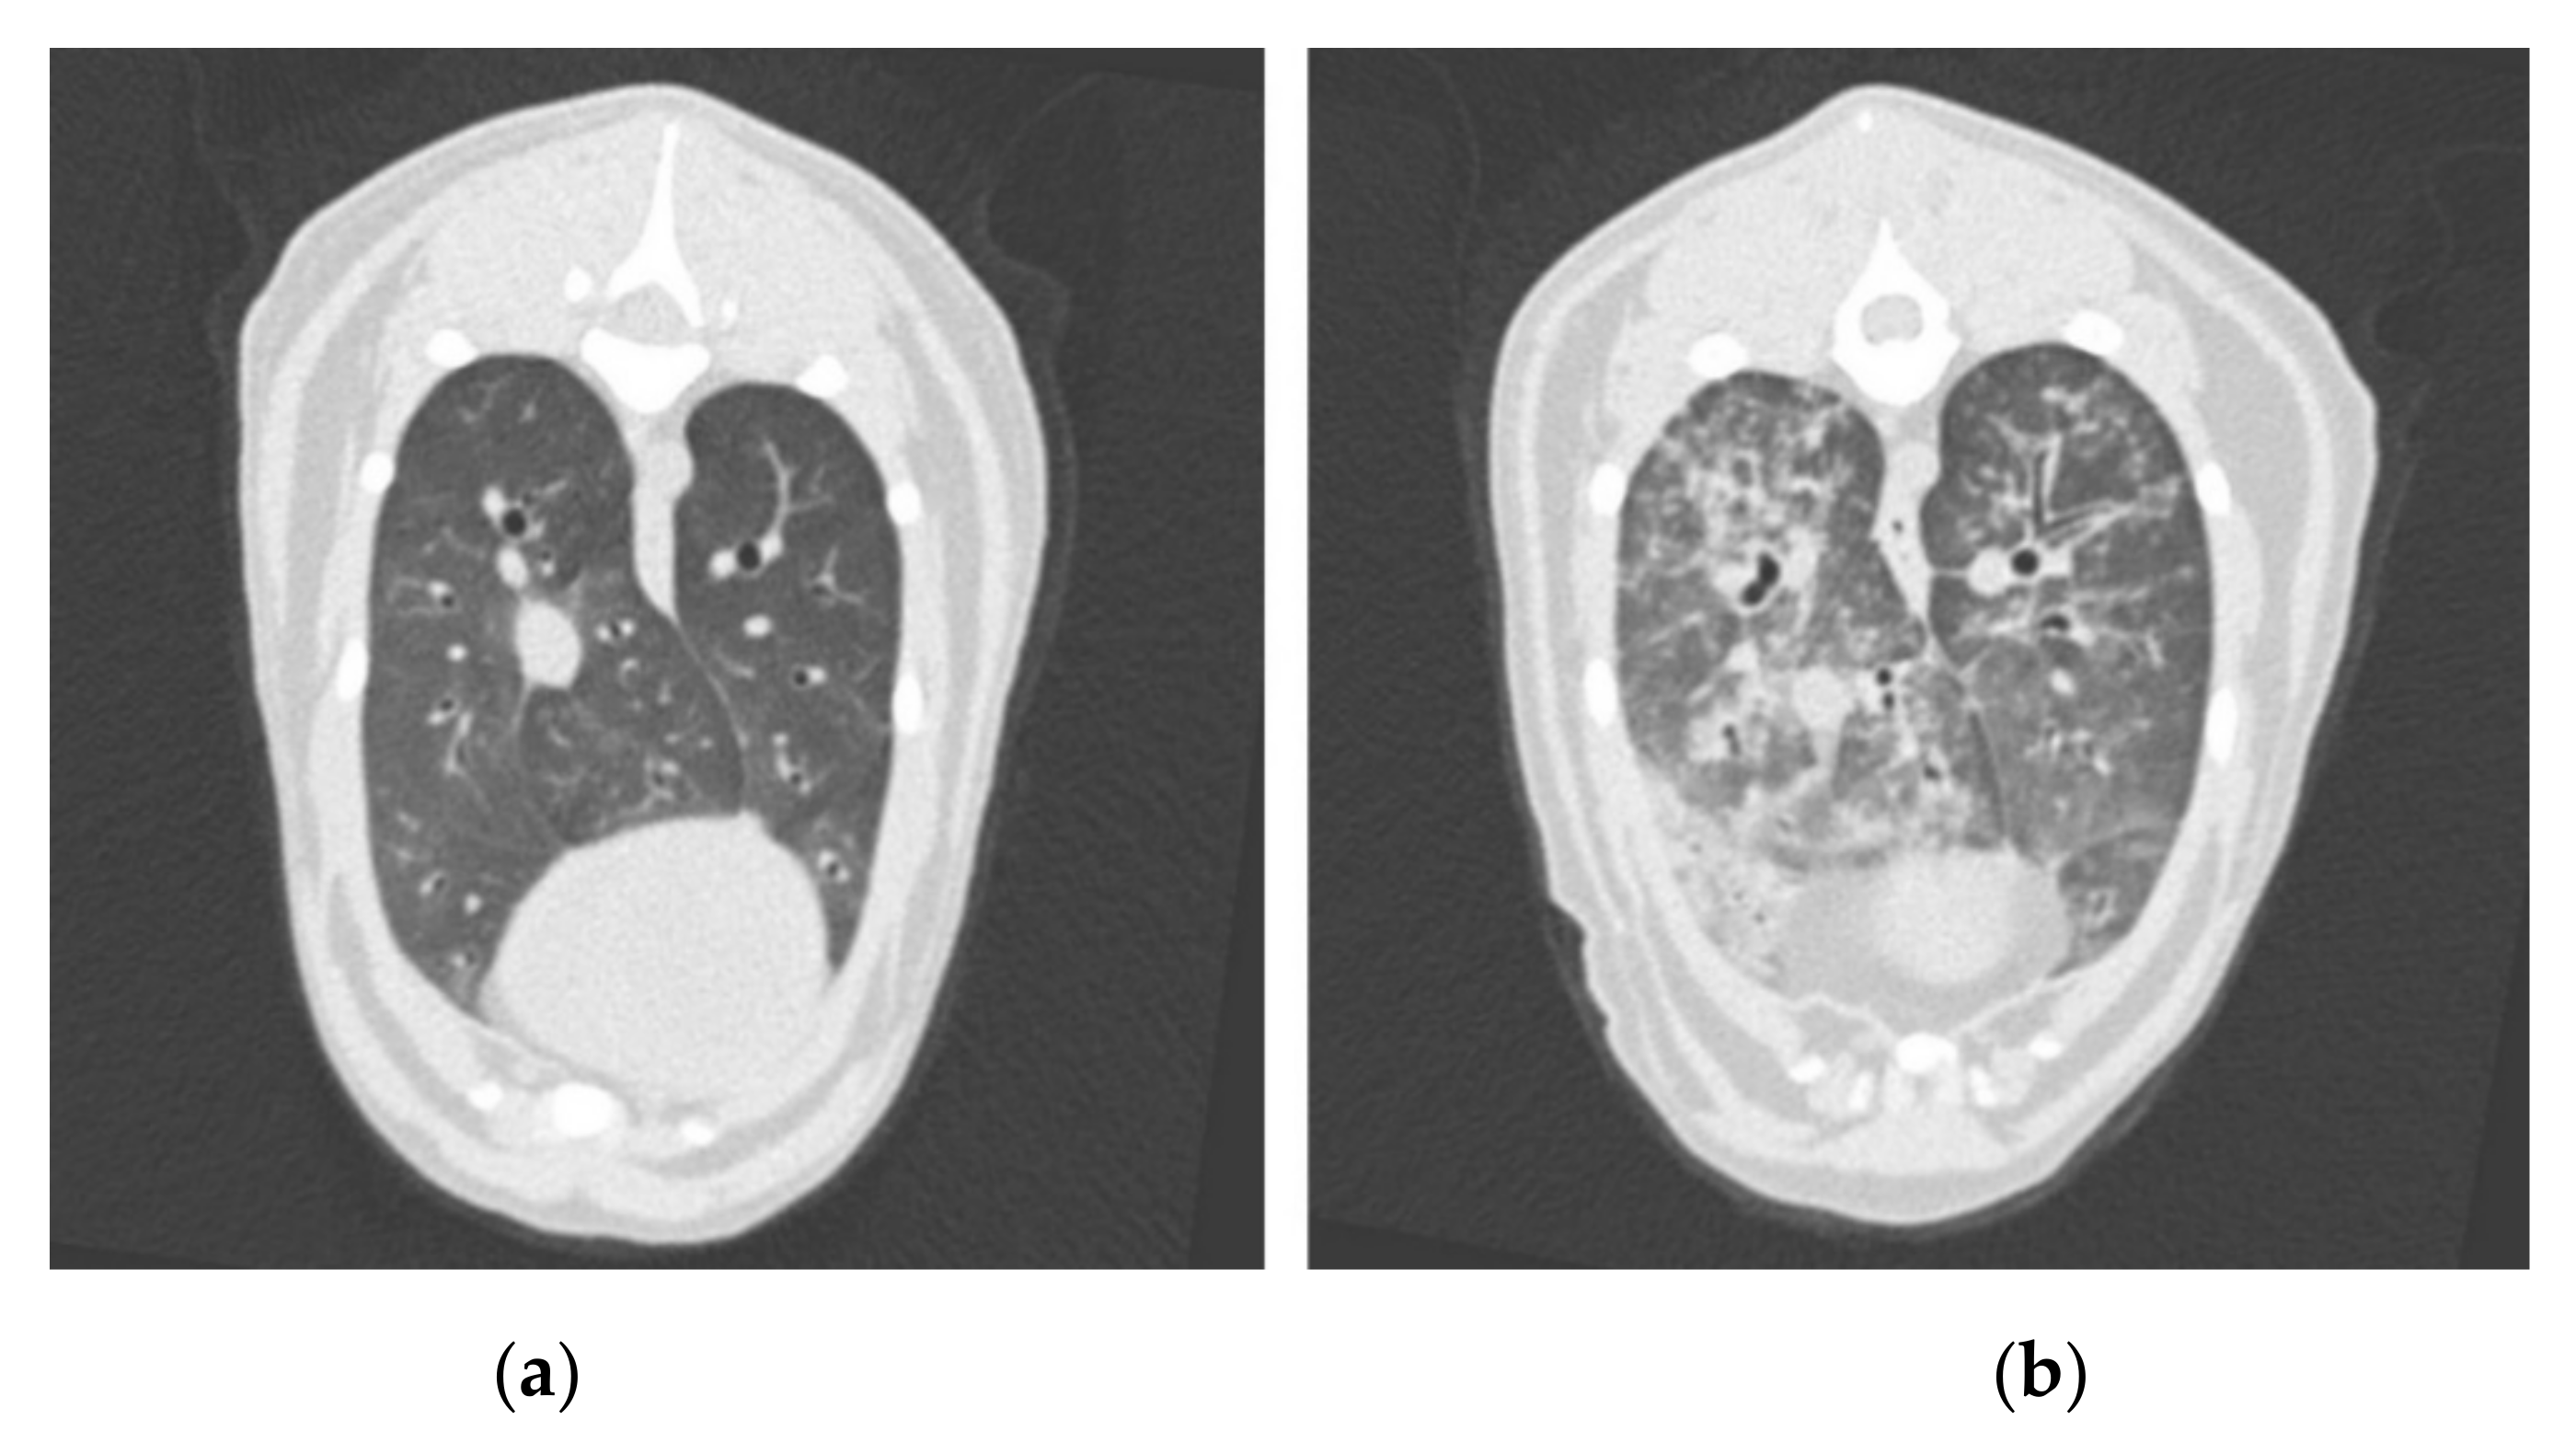

2.4. Computed Tomography

| CT Lung Severity Score | Imaging Features |

|---|---|

| 0 = normal | No changes |

| 1 = mild | Some or all zones affected, some areas of ground-glass opacity, only occasional nodules or consolidated areas, mild reticular and/or mosaic pattern, no or mild bronchial wall thickening, no lymph node enlargement |

| 2 = moderate | All zones affected, some or multiple areas of ground-glass opacity, multiple or all lobes affected, occasional consolidated areas, no or some nodules, moderate reticular and/or mosaic pattern, bronchial wall thickening, partial loss of visual separation between bronchial walls and peribronchial vessels, enlarged lymph nodes |

| 3 = severe | All zones affected, multiple nodules or general nodular pattern, multiple consolidated areas, severe reticular and/or mosaic pattern bronchial wall thickening, marked ground-glass opacity, loss of visual separation between bronchial walls and peribronchial vessels, enlarged lymph nodes |